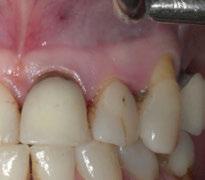

directamente a cabeza de implante para realizar una prótesis dentoalveolar de cerámica de 3 piezas, que equilibraran la oclusión y dieran soporte al labio y la mejilla (Figuras 14-17)

Durante el primer mes tras la intervención la paciente presentó epífora del ojo izquierdo que se resolvió de forma espontánea. Al año acude a consulta refiriendo dolor localizado y celulitis subcutánea originada por tejido de granulación en el brazo de la conexión más anterior.

Tras realizar curetaje quirúrgico periimplantario y tras una semana

de tratamiento antibiótico con amoxicilina y ácido clavulánico, cede la infección. Al segundo año de seguimiento, el tratamiento permanece estable y no ha presentado más complicaciones biológicas, estructurales o protésicas.

Figura 14. Imagen intraoral frontal postoperatoria al año de la reconstrucción.

Figura 15. Detalle de prótesis dentoalveolar cerámica en visión lateral.